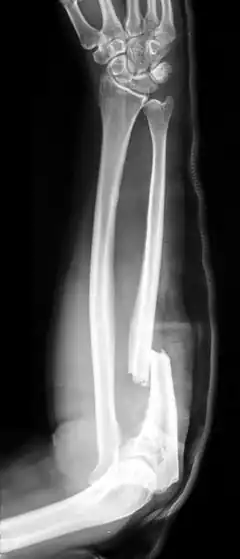

X-ray of Monteggia fracture of right forearm | |

The Monteggia fracture is a fracture of the proximal third of the ulna with dislocation of the proximal head of the radius. It is named after Giovanni Battista Monteggia.[1][2]